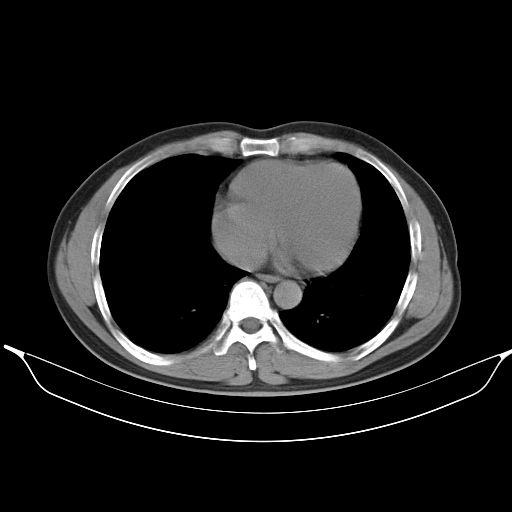

标题: CT25490:男,40岁,体检发现;无其它不适。 [打印本页]

标题: CT25490:男,40岁,体检发现;无其它不适。

支持 !考虑右下肺周围性肺癌并肺内多发转移,纵隔淋巴结转移,(气管前腔静脉后,隆突下,主动脉弓下都有了)

考虑右下肺周围性肺癌并肺内多发转移,纵隔淋巴结转移!